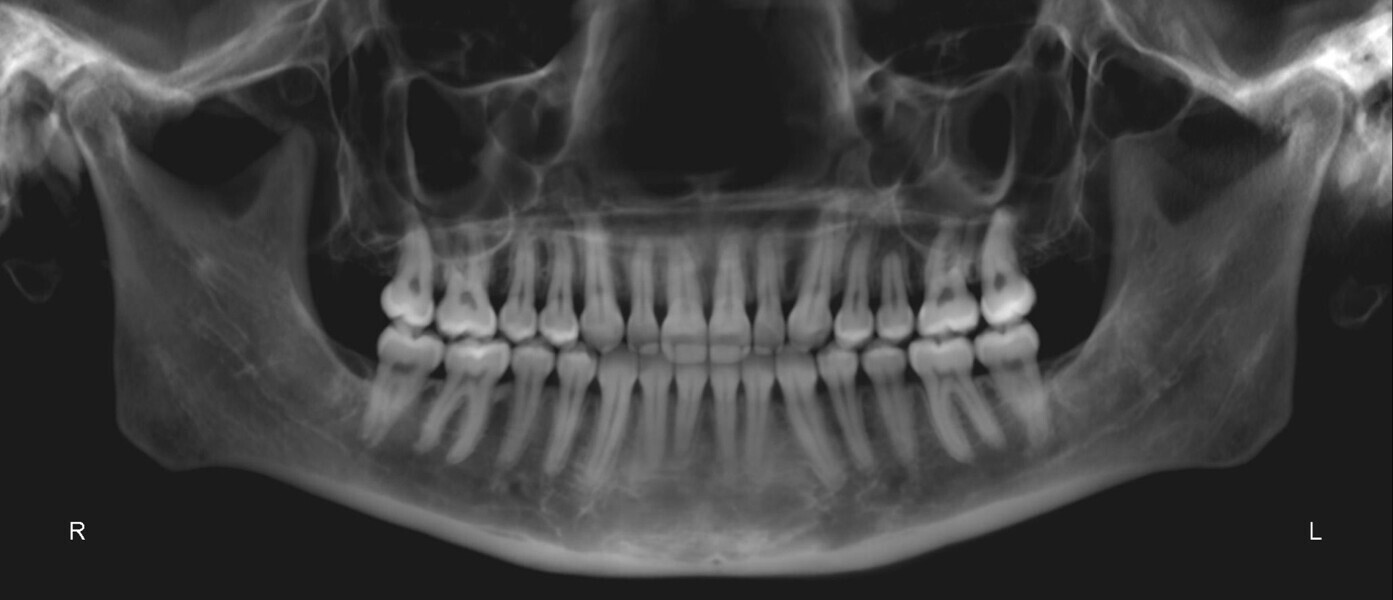

The panoramic radiograph showed prior extraction of all third molars, localised root resorption of several teeth, generally good periodontal health and an atypical condylar morphology, suggestive of temporomandibular joint (TMJ) remodelling or degenerative changes (Fig. 19). The cephalometric radiograph and tracing revealed a mesobrachyfacial skeletal pattern and a tendency towards a Class II skeletal pattern (Fig. 20).

The panoramic radiograph revealed the absence of third molars and good root morphology and parallelism (Fig. 37). The cephalometric radiograph and tracing indicated a Class III skeletal pattern tendency, characterised by a short cranial base and a long mandible. The maxillary incisors were retroclined, and the mandibular incisors were proclined (Fig. 38).

TMJ analysis

The patient reported joint and orofacial muscle pain, headaches, neck pain and nocturnal bruxism. CBCT imaging showed small condyles with flattened articular surfaces. The right condyle was slightly posteriorly positioned within the mandibular fossa (Fig. 39). Additionally, a virtual articulator mounting using the MODJAW system revealed that there was a significant discrepancy between maximum intercuspation and centric occlusion and that the first occlusal contact was at tooth #27 (Fig. 40).